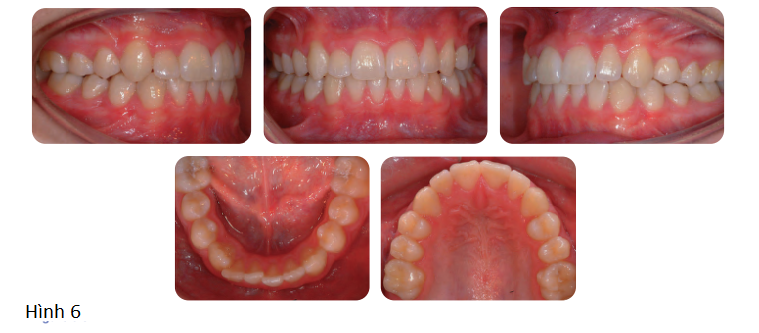

Kết quả cuối cùng: Hình 6